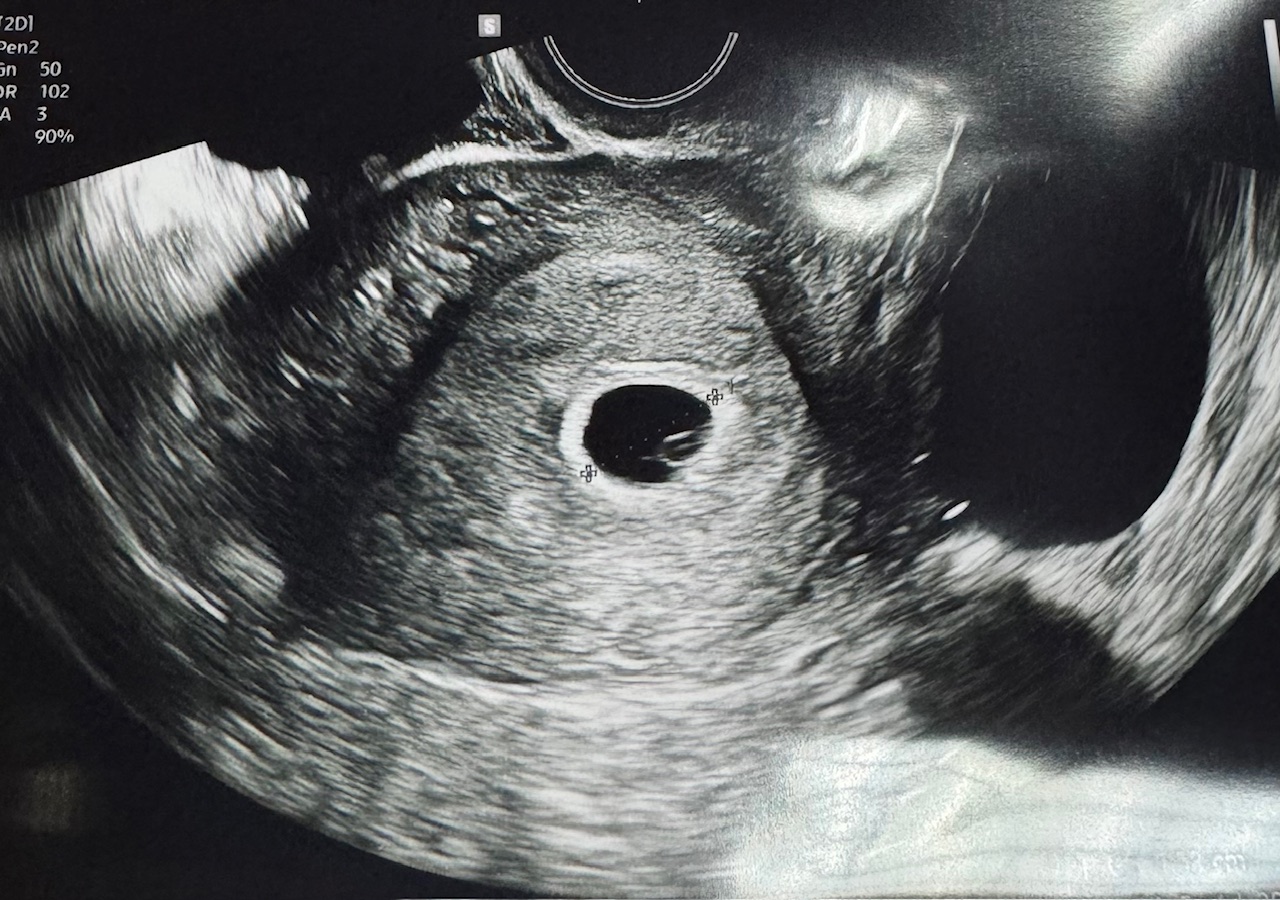

난항 사진과 태명

잘 크고 있는 우리 아기, 무사히 난항까지 확인했습니다.

이제 조금 더 실감이 나네요.

우리 아기의 태명은 "뽀물이"로 정했어요.

작고 귀엽게 잘 자라주기를 바라는 마음을 담았답니다.